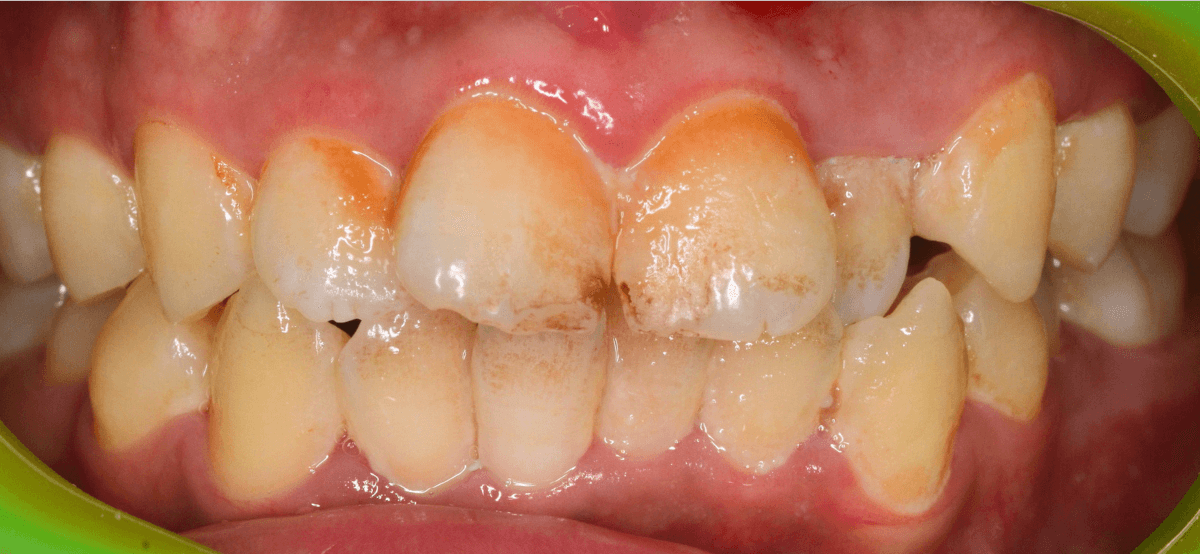

Case.2

今回は、上の前歯の縁下歯石の除去をしたお話です。

写真の左の矢印の歯肉が退縮して腫れています。

右の矢印の歯肉と比べてみるとわかると思います。

こういった歯肉の形をしている部分は、歯石がたまっていることが多いです。

拡大してみると、縁下歯石(歯肉の中に入り込んだ歯石:歯肉に大きく悪影響を与えます)が顔を出しているのがわかります。

かなり歯肉の中に歯石が入り込んでしまっていると思われます。

歯肉の中の歯石は歯にべっとりとこびりつきますので、除去するには麻酔をして引きはがす処置が必要です。